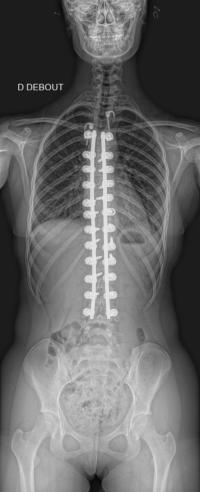

Images de scolioses opérées 16 janvier 202418 janvier 2023 par Damien Scoliose thoraco-lombaire 1 Radio préopératoire de Face Radio préopératoire de Profil Radio de Face à 2 ans de recul Radio de Profil à 2 ans de recul